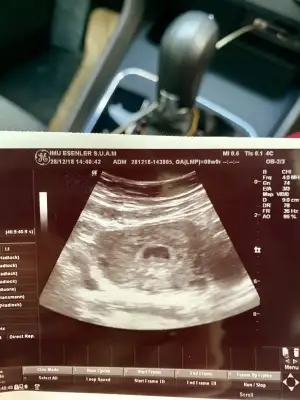

MERHABA TEKRAR BUGUN BASKA DOKTORA GİTTİM Bİ TANESİNİN KALP ATİSİNİ DUYDUK DİGER KESEYİDE GORDUK AMA O UFAK GELİSEMEYEBİLİR DEDİ SİZDE BOYLE OLAN VE GELİSEN VAR Mİ